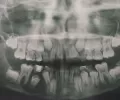

Во вложении есть снимок 6 зуба с левой стороны, врач говорит, что это киста и предлагает два варианта: лечение и гаймороскопия или удаление зуба и гаймороскопия. На 4,5 и 6 стоят коронки.

Что бы Вы посоветовали в данном случае?

Зуб однозначно требуется удалить, и через 3-4 месяца принять решение по поводу операции.